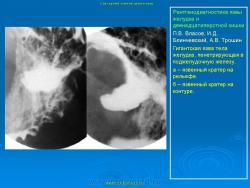

Пищеварительная система. Рентгенодиагностика язвы желудка и 12-ти перстной кишки. +

Рентгенодиагностика язвы желудка и 12-ти перстной кишки.